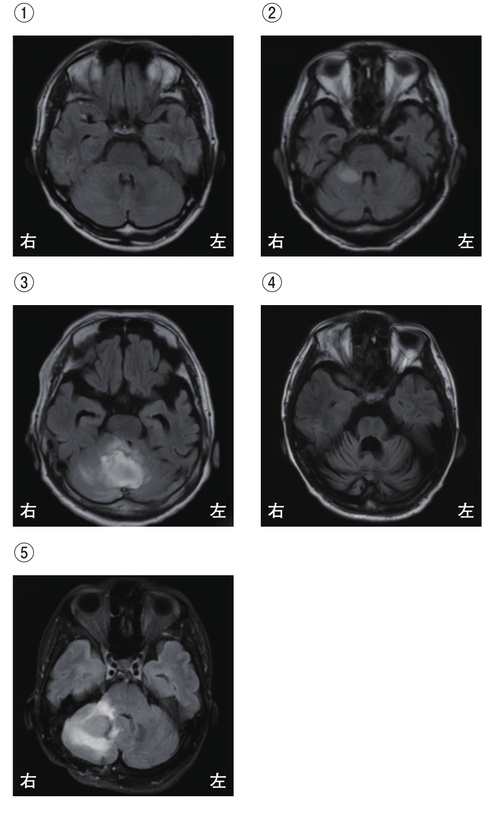

5

理学療法士実地問題 -

第58回 午前

重要度:重要

42歳の女性。最近、手の震え、歩行時のふらつきがひどくなり、神経内科を受診した。精査の結果、脊髄小脳変性症と診断された。頭部MRI を別に示す。頭部MRIの画像で正しいのはどれか。

1

①

2

②

3

③

4

④

⑤

6

第57回 午前

重要度:最重要

78歳の男性。脳梗塞。左顔面神経麻痺および右片麻痺を呈する。頭部MRIの拡散強調像を示す。梗塞巣として考えられるのはどれか。